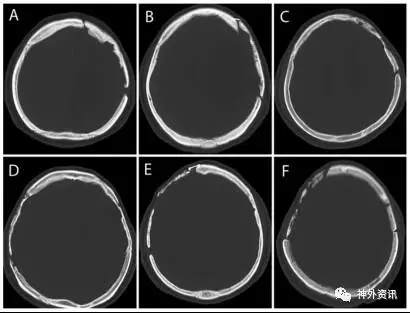

自2001年1月至2012年12月该医院为188例患者采用211块保存在聚维酮碘的冷冻自体骨瓣进行颅骨修补术。自体骨瓣取自开颅手术,用生理盐水洗净后置于无菌手套中,浸泡在0.5%的聚维酮碘溶液。经过一系列处理,注明患者姓名、性别、年龄、住院号和手术日期等,保存在-20°C的冰箱内备用。188例患者术后有8例骨瓣感染,2例在两年随访期间死亡,故将该10例剔除。其余178例患者使用201块自体骨瓣,被纳入研究。178例患者使用的201块自体骨瓣根据CT扫描显示骨瓣骨质吸收状况分成3种类型,骨瓣变薄的I型、骨瓣骨密度降低的II型和骨瓣溶解的III型(图1、2、3)。

图1. 骨瓣变薄的I型:特点是骨瓣变薄和骨间隙增宽。骨瓣吸收程度分为轻度(A)、中度(B)或重度(C和D)。D组骨瓣显示严重的骨间隙增宽,但只有轻微的骨瓣变薄。

图3. 骨瓣溶解的III型:其特点是有限的或广泛的骨质溶解,表现为虫蛀状。A和B为骨密度轻度吸收,C为骨密度中度吸收,E和F为骨密度重度吸收。